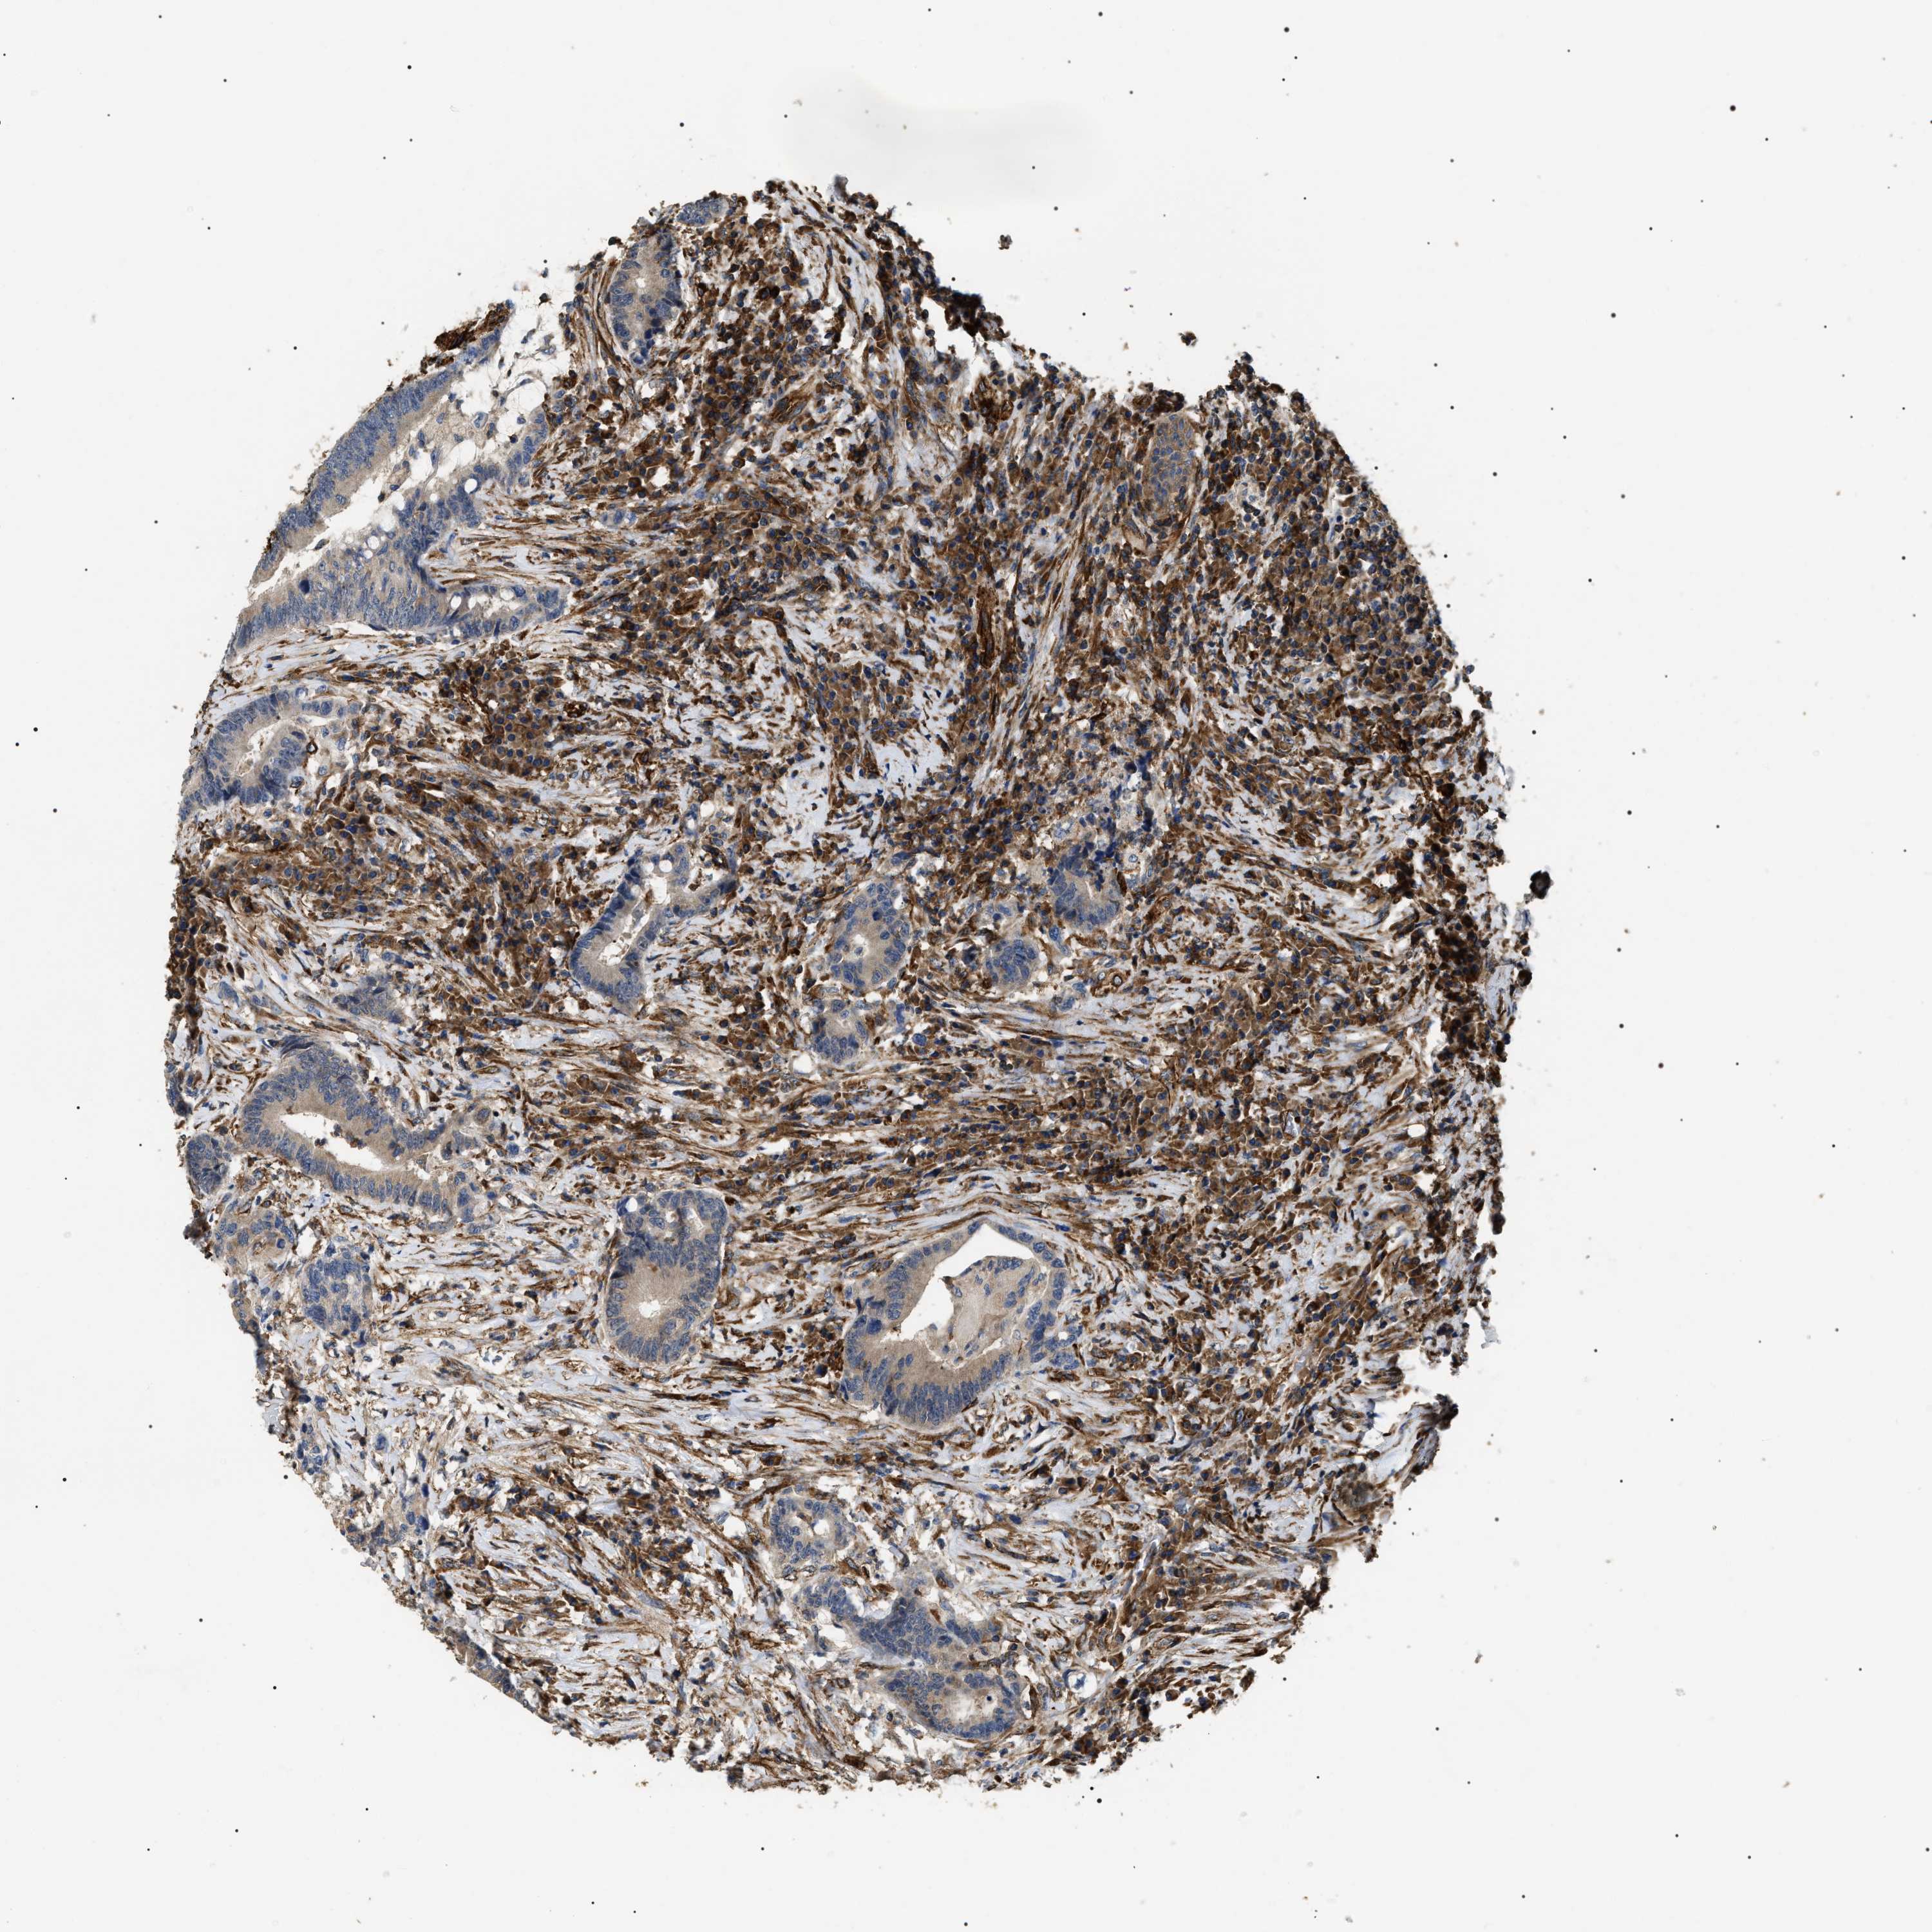

CANCER COLORECTAL CANCER Show tissue menu

Colorectal cancer

Colon adenocarcinoma